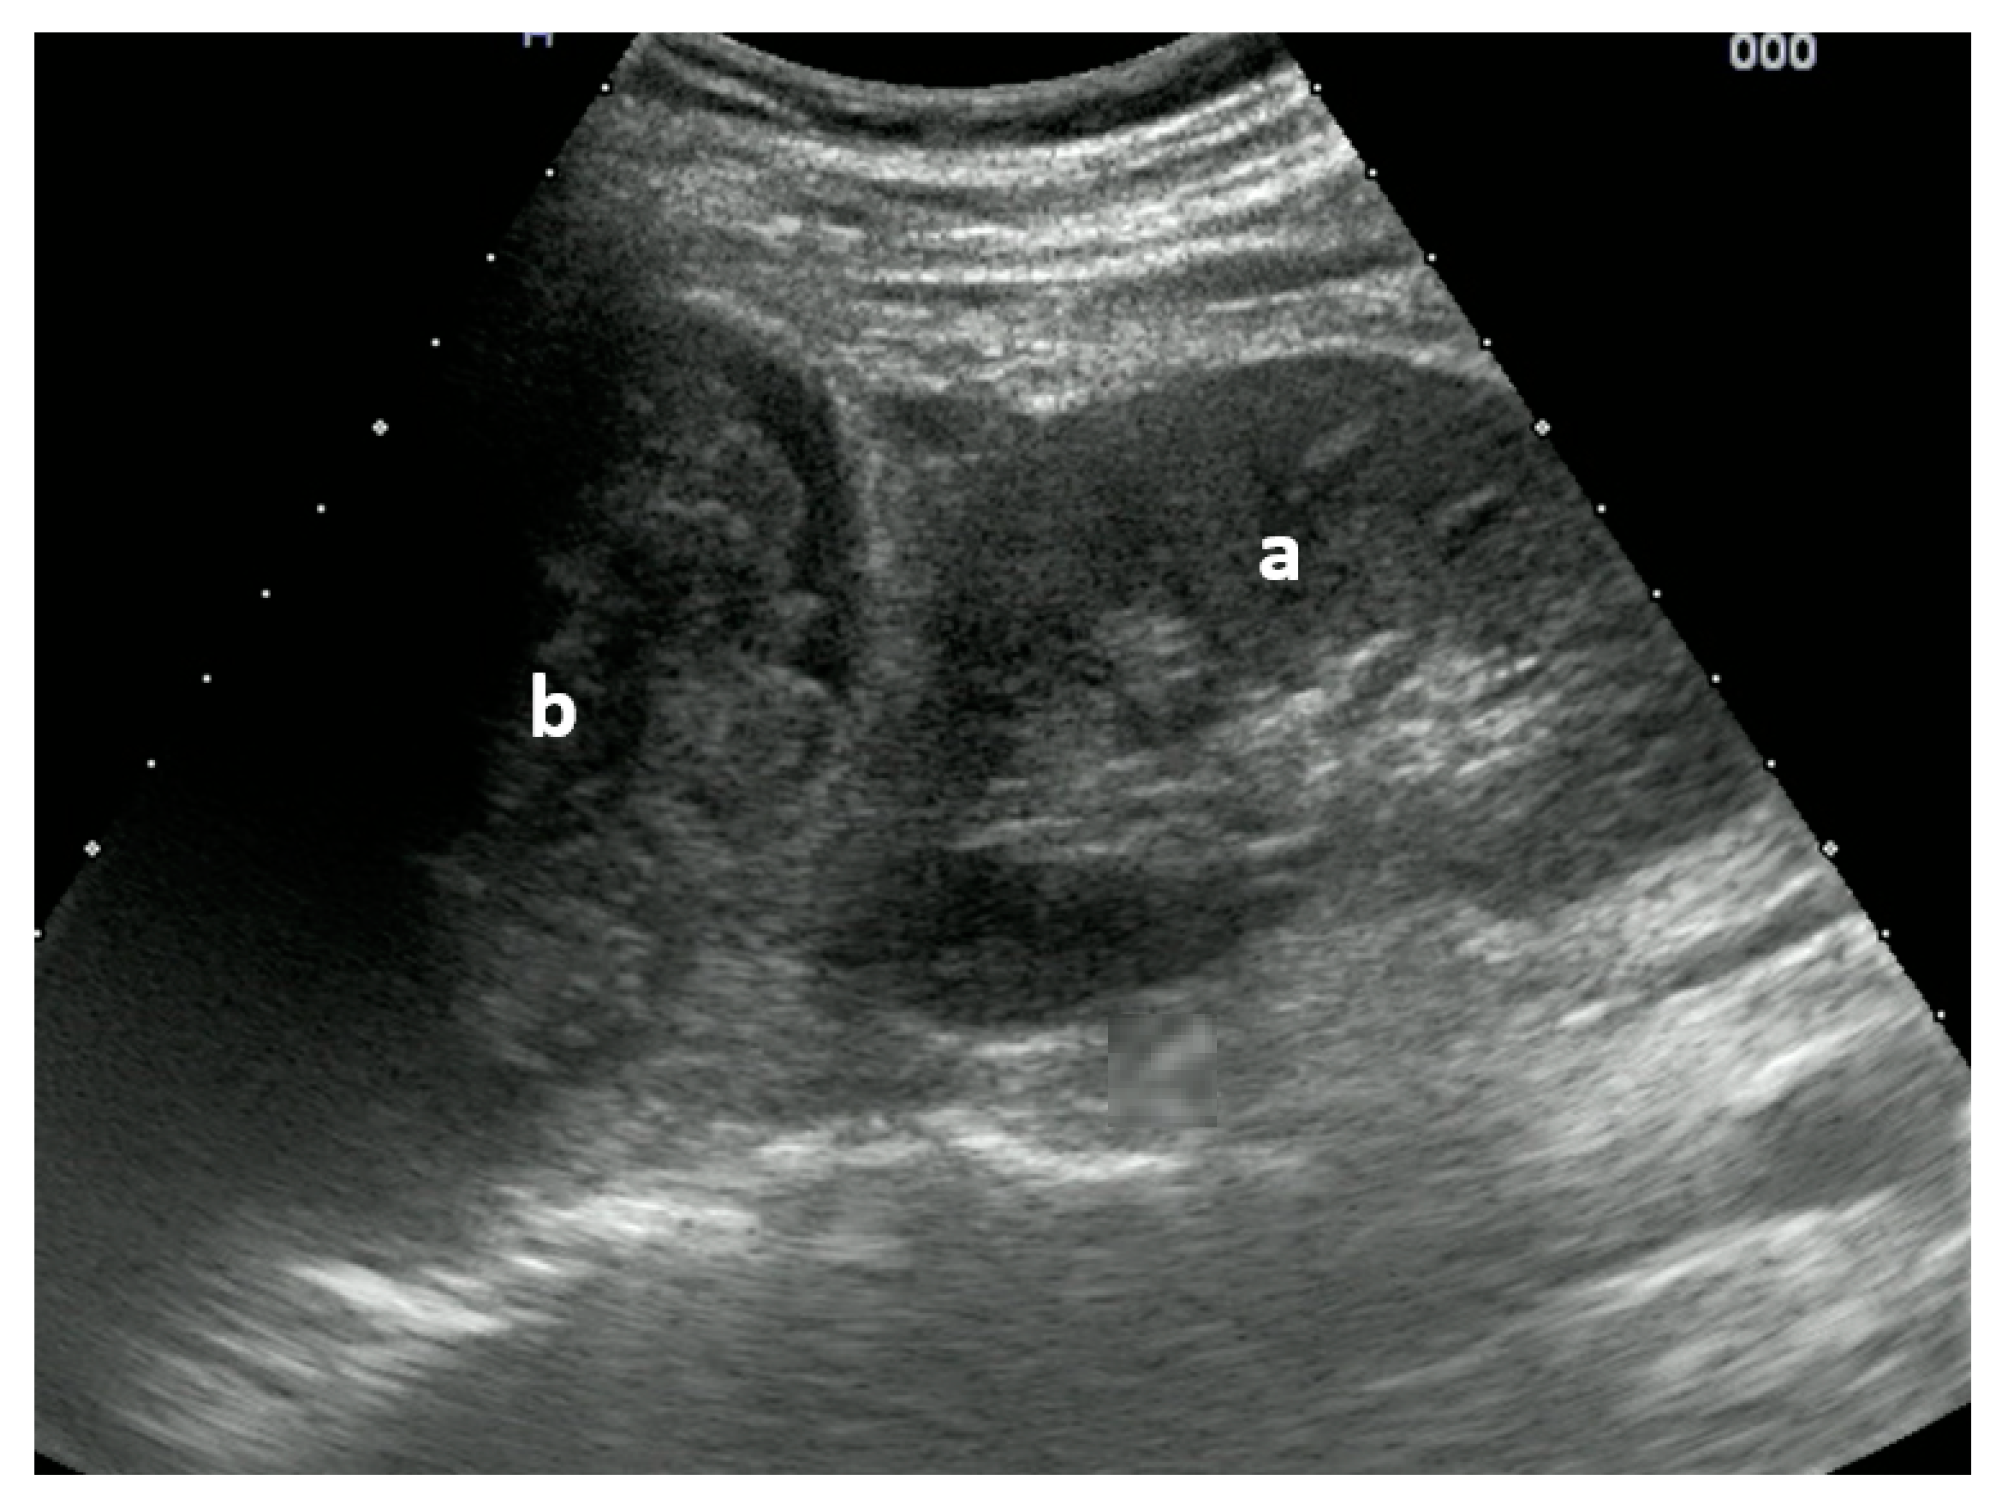

Figure 3.

Right upper quadrant view: (a) kidney with traumatic adrenal gland hemorrhage and retroperitoneal hematoma (b). Image courtesy of J. Osterwalder.